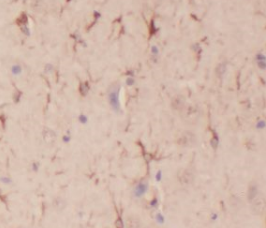

| 验证图片 | Immunohistochemistry of paraffin-embedded human brain using FNab06062(DCTN1 antibody) at dilution of 1:50 human brain tissue were subjected to SDS PAGE followed by western blot with FNab06062(DCTN1 antibody) at dilution of 1:500 |